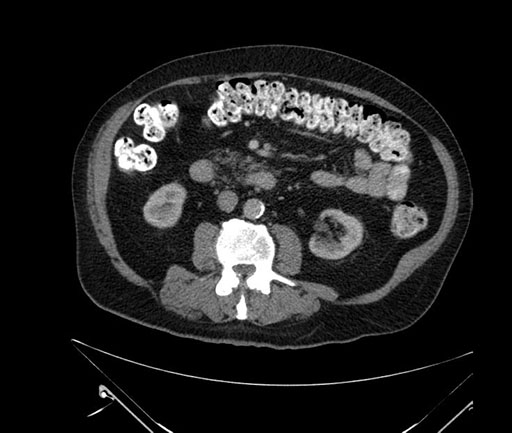

Imaging Analysis

Look through the patient's CT scan to identify any areas of concern for the necessary procedure.

Based on your CT findings, which issue(s) would give reason for "planned slowing down moment(s)" in this case?